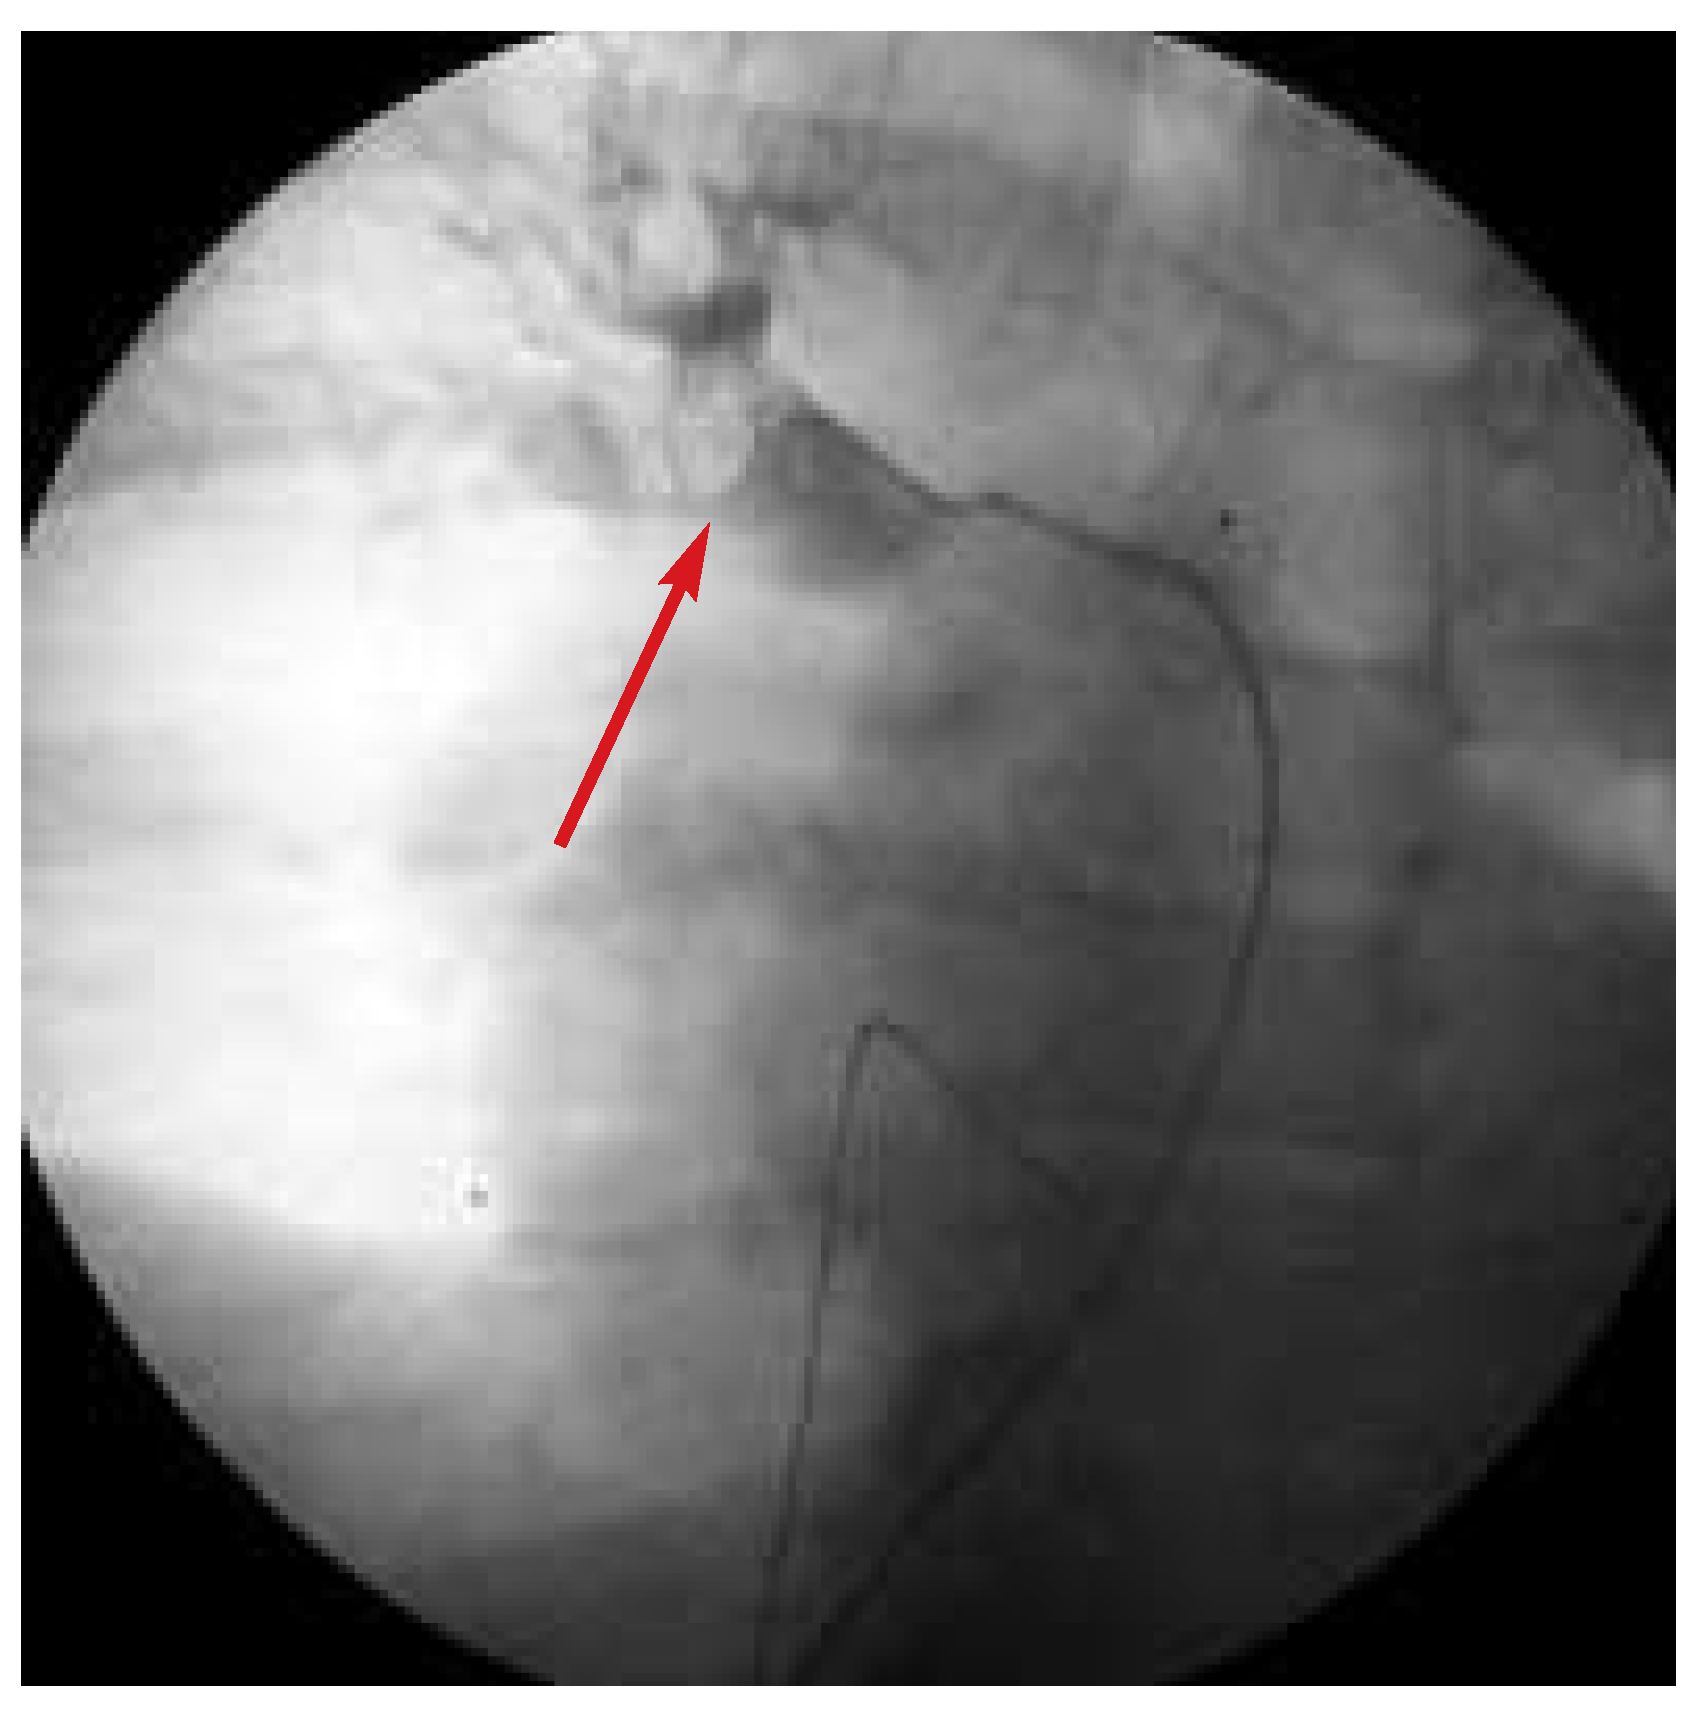

Abbildung 2. Nicht-selektive Pulmonalis-Angiographie (Pigtail 6 F) mit auffälliger Amputation zahlreicher ar-terieller Lungensegmente (Markierung), insbesondere der oberen rechten und der gesamten linken Strombahn.

Ein 60jähriger Mann ohne bekannte kardiovaskuläre Risikofaktoren stellte sich mit seit einigen Wochen zunehmender Dyspnoe in der Notaufnahme vor. Schon bei Spitaleintritt waren die Kriterien eines kardiogenen Schocks erfüllt: Der systemische Blutdruck betrug 80/60 mm Hg, die Herzfrequenz 110/min, auffällig waren zudem massiv gestaute Halsvenen. Aufgrund des Rechtsschenkelblockbildes im EKG mit S1—Q3-Phänomen (Abb. 1) sowie einer massiven Dilatation der rechten Herzkammern in der Echokardiographie stellten wir die Verdachtsdiagnose einer zentralen, lebensbedrohlichen Lungenembolie und leiteten eine systemische Fibrinolyse mit r-tPA (front loaded) ein. Leider führte diese Massnahme nicht zu einer klinischen bzw. hämodynamischen Besserung des mittlerweile kritischen Zustands des Patienten, so dass rasch ein chirurgischer Eingriff bzw. eine mechanische Desobstruktion der Lungenzirkulation in Erwägung gezogen werden musste. Da die Herz-Lungen-Maschine wegen einer gleichzei-tig stattfindenden Bypass-Operation nicht zur Verfügung stand, entschieden wir uns für eine mechanische, endoluminale Fragmentierung und damit Mobilisierung des thrombotischen Materials. Zwischenzeitlich machten zunehmende, therapierefraktäre Bradykardien die Einlage eines provisorischen Herzschrittmachers notwendig. Schliesslich zeigte die nicht selektive Pulmonalis-Angiographie (Abb. 2) eine fast vollständige Amputation beider pulmonal-arterieller Gefässstämme. Mit verschiedenen Kathetern versuchten wir die ausgeprägten thrombotischen Ablagerungen zu zerkleinern und damit zu mobilisieren, allerdings nur mit partiellem Erfolg (Abb. 3). Der Patient verstarb schliesslich nach einer prolongierten Reanimation in Folge einer elektromechanischen Entkopplung.